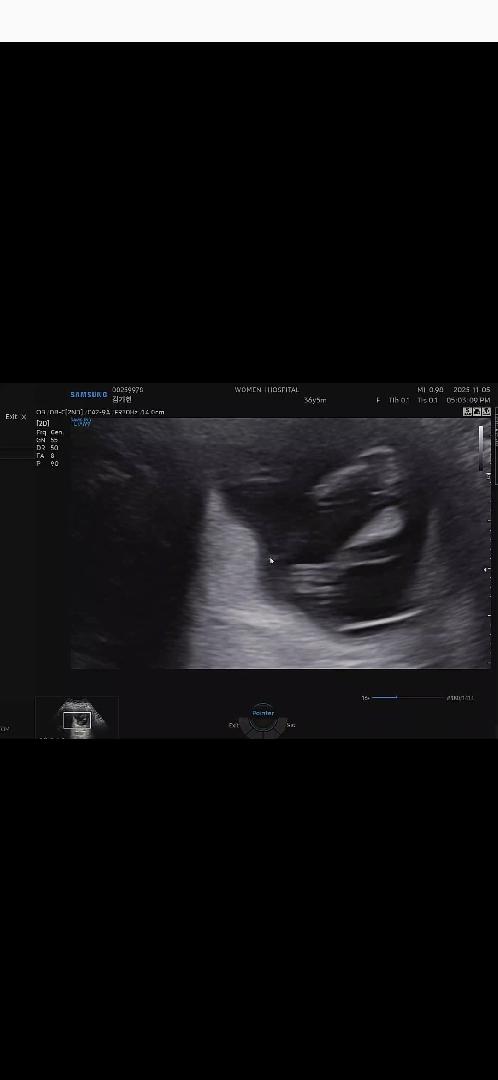

13주 1일차에요 성별 뭐일지 너무 궁금해요

성별 뭐든 상관없지만 너무 궁금하네요